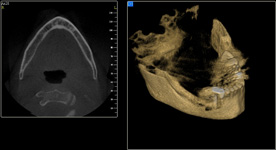

Tento výkon se nazývá sinus lift - aplikace kostního granulátu do čelistní dutiny

Při ztrátě molárů a premolárů v horní čelisti a jejich náhradě implantáty se často setkáváme s nedostatečnou vertikální nabídkou kosti pod čelistní dutinou, často doprovázenou i nedostatečnou horizontální nabídkou a sníženou kvalitou kosti

(v oblasti 2. premoláru v 50%, v oblasti moláru až v 80% případů nedostatečná kostní nabídka)

Od roku 1985 je tento problém řešen augmentační operací nazývanou sinus lift.

Jedná se o vyzvednutí membrány, která čelistní dutinu vystýlá, pod vyzvednutou membránou vznikne kapsa, kam se umístí augmentační materiál, do kterého se zavedou implantáty.